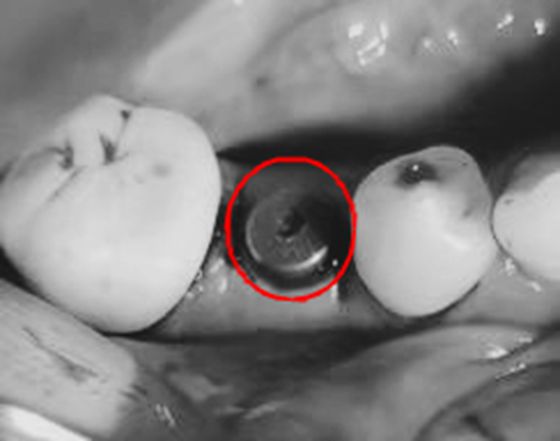

根据易大姐目前的病情,朱彬医师请口腔外科向峰医师会诊,共同为易大姐制定了合适的治疗方案:首先针对口内多颗坏牙再次填充治疗,同时拔除右下方的残牙断根,植入人工牙根。朱彬医师为患者完成了口内坏牙的充填治疗后,向峰医师在不到一小时的时间里将烂牙根替换成人工牙根,牙龈仅缝合2针,坏牙填充无缝与人工牙根植入无缝连接,一气呵成。期间易大姐未有任何疼痛和不适感。3个月后,易大姐便可以任意食用美食了。

向峰医师介绍,将口内不能保留的患牙即刻拔除,然后即刻植入种植体大大缩短了拔牙及镶牙的治疗时间,最重要的是避免了因拔牙后出现的骨吸收,为植入种植体保留了牙槽骨的高度和宽度。此次种植也充分利用牙龈的缺损区将愈合基台接入口腔,避免了种植的2期手术愈合基台的接入,一次性解决多个问题。